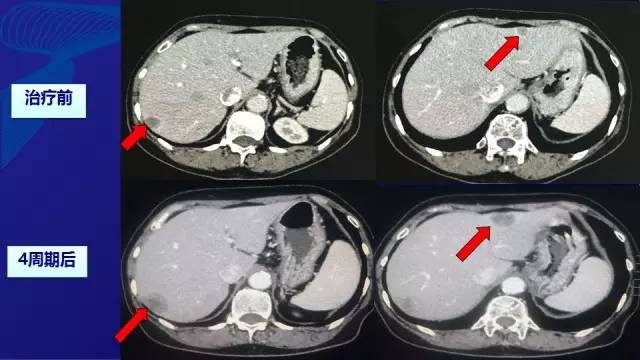

● 由于经济原因拒绝使用靶向药物,予XELOX方案化疗(减量) –奥沙利铂:100 mg/m2, d1 –卡培他滨:850 mg/m2,BID, d1-d14。无严重不良反应。

● 2周期—SD; 4周期—PD